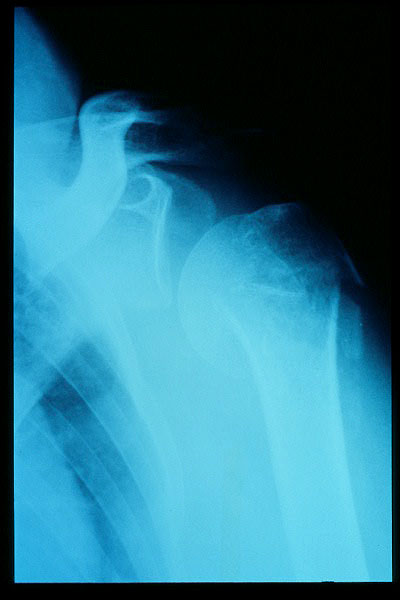

Fractura impactada de húmero .